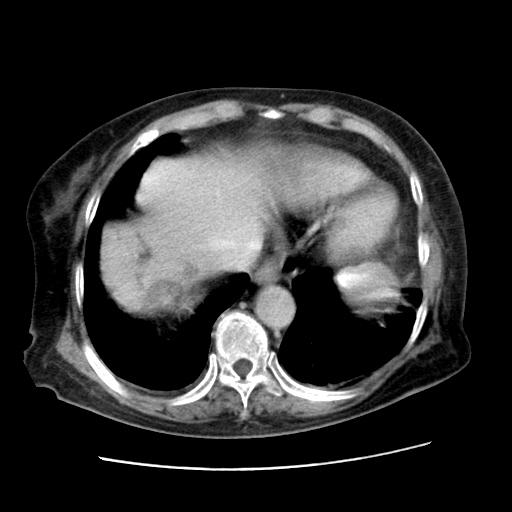

女,77.无不适

肝内胆管扩张,胆囊炎,胆囊窝积液。 右侧胸腔少量积液。

右侧胸腔少量积液(也可能是胸膜增厚不过是什么都一样)

肝右叶肝内胆管结石并肝内胆管扩张。胆总管下段梗阻,考虑壶腹部占位。支持